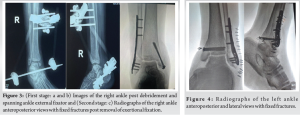

The patient was booked urgently for debridement and external fixation of the open fracture and open reduction and internal fixation of the closed fracture with plate and screws. These procedures were done in the same setting approximately 36 h post the injury. A thorough debridement was performed, and a cross-ankle external fixator was applied for the right ankle utilizing an Ortho-XACT trauma frame (Fig. 3a and b). On the left, a plate and screws were used for fixation of the lateral malleolus, and two cannulated screws were used for fixation of the medial malleolus (Fig. 4). A second stage was performed on the right ankle. The external fixator was converted to a definitive open reduction and internal fixation using a plate and screws approximately 2 weeks (16 days) later (Fig. 3c).